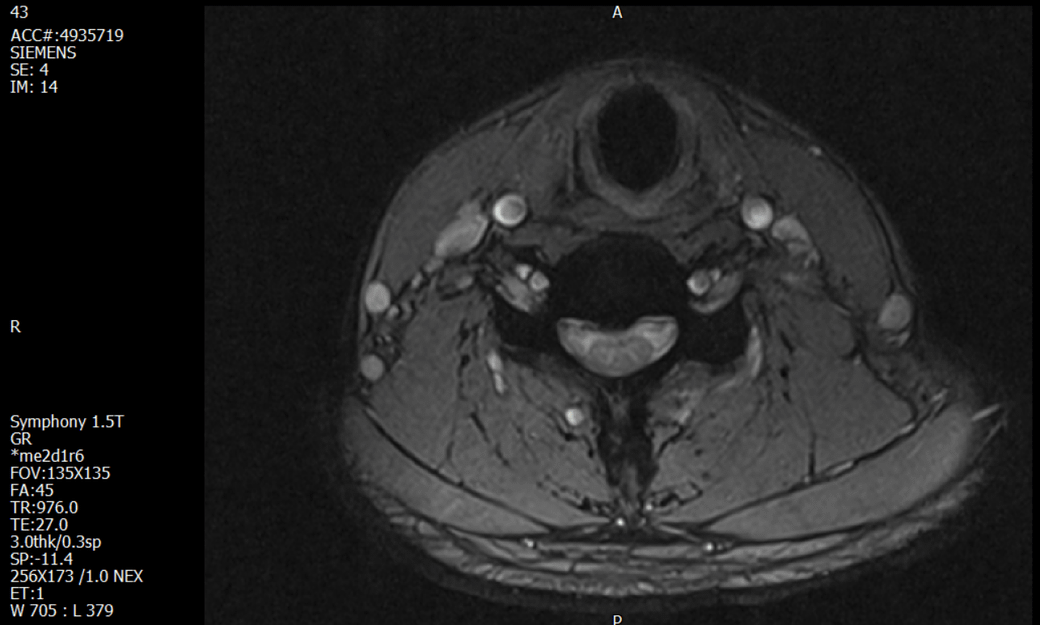

경추 요추 디스크 MRI판독 부탁드립니다.

- 3개월전 좌측 상지 저림(힘빠짐) 발생. 이틀뒤 에 좌측 하지 저림(힘빠짐) 발생.

(힘이 축처지는 느낌이라서 힘빠짐이라고 하지만, 실제 근력 문제, 감각이상, 활동 문제 없음)

-11월, 증상발생 직후 잠실소재 척추전문병원 MRI 요추경추 촬영 후 신경외과 박사 진료, 허리는 매우 건강, 경추는 퇴행성 진행되고 있지만 디스크라고 보기 어려움. 신경막만 살짝 건드리는 정도고 이 정도로 힘빠짐이나 저림이 오지 않고 원인은 다른 곳에 있을 가능성.

-12월, 분당서울대병원 재활의학과 진료, MRI 영상보고 딱히 다른 말은 없었음. 근전도 검사해보자 해서 신경전도, 근전도 검사 진행, 검사결과 이상없었고, 신경쪽 문제는 아예 배제해도 될것이라고 함. 정신쪽에 기인한 문제일 가능성 제시.

-올해 1월, 국립암센터 재활의학과 진료, 병명을 찾기가 쉽지 않을 것

-올해 1월, 분당서울대병원 신경과 진료, MRI영상보더니 디스크가 있고 저림과 힘빠짐이 이에 기인했을 가능성이 충분히 있다고함. (경추만 말한것인지 요추도 포함인지 모르겠으나 디스크 시술 방안을 제시함) , 팔다리가 우연이 동시에 저림이 올수 있는지에 대해서 물었더니 이틀 상간으로 발생했기 때문에 동시라고 보기 어렵다고함...

1. MRI 상 , 경추와 요추에 디스크가 있나요? 있다면 좌측 팔과 다리에 저림 및 힘빠짐을 줄 정도인가요?

• 1. MRI 사진을 보았을 때 디스크를 의심해볼 수 있는 소견이 살짝살짝 보이긴 합니다만, 상하지의 저림 및 힘빠짐을 유발할 정도인지는 솔직히 회의적입니다.

2. 영상의 퀄리티는 나쁘지 않아 보입니다. 굳이 재촬영을 하실 필요는 없어 보입니다.

3. 개인적으로는 디스크로 인한 증상이 아닐 것으로 보나, 만약 디스크가 맞다면 우연하게 목과 허리 디스크 발병이 이틀 간격을 두고 나타났을 가능성을 생각해야 하는데, 현실적으로 그 가능성이 높지 않습니다.

4. 말씀하신 것처럼 특히 요추부 MRI는 디스크를 찾기 어렵습니다.

상기 MRI 소견으로는 심한 증상을 보일 정도는 아니며 디스크의 가능성은 적어보입니다.